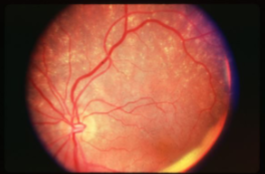

geographic or central areolar RPE atrophy

a form of dry AMD consisting of large areas of GA of the RPE

histologic: the area of GA is associated w/ focal loss of the retinal receptor cells, RPE, & choriocapillaris

5-10% of pts w/ AMD lose central vision as a result of this form of AMD

one or more sharply circumscribed geographic areas of atrophy of the RPE & retinal in the posterior pole

central vision is slow & progressive as the atrophic concentric area enlarges

bilateral, symmetric

20% of these pts will develop CNVM in the 2nd eye

FA shows varying degrees of loss of the choriocapillaris w/in the area of GA

GA

GA

GA

GA

GA